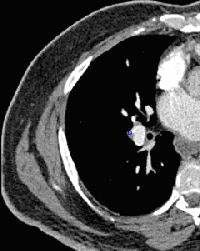

![]() |

| Notice both medial and lateral subsegmental PE (bottom right) found by CAD but missed by inexperienced readers. |